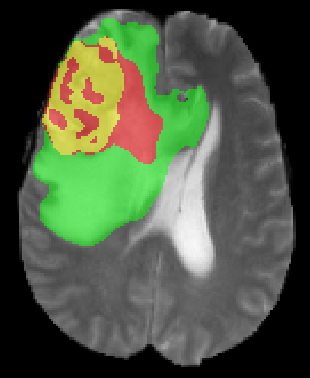

We argue that the sub-optimal paradigm of processing different abstractions within a single CNN pipeline can be remedied through the effective processing of information in a structured manner. Consequently, we devise strategies for disentangling the edge and texture information within a single training pipeline. Figure 2 illustrates how our proposed module, dubbed EG-CNN, can be paired with any existing CNN encoder-decoder to improve segmentation quality near intensity edges. We have applied our EG-CNN to the tasks of brain and liver tumor segmentation in medical images (Figure 3).

(1) Brain MR (2) Liver MR (3) Liver CT (4) Lung CT

We first introduce a method for connecting the output of a CNN to an ACM, yielding a model for the precise delineation of lesions, to which we refer as Deep Active Lesion Segmentation (DALS) (Figure 4). We then go further to introduce a truly unified framework (Figure 5) that bridges the gap between ACMs and CNNs by leveraging a novel, automatically differentiable level-set ACM with trainable parameters that allows for back-propagation of gradients and can be end-to-end trained along with a backbone CNN from scratch, without any CNN pre-training. The ACM is initialized directly by the CNN and utilizes an energy functional that is locally-tunable by the backbone CNN, through 2D feature maps. Thus, our work overcomes the big hurdle of fully automating the powerful ACM approach to image segmentation. We have applied our proposed framework to the task of building segmentation in aerial images (Figure 6).